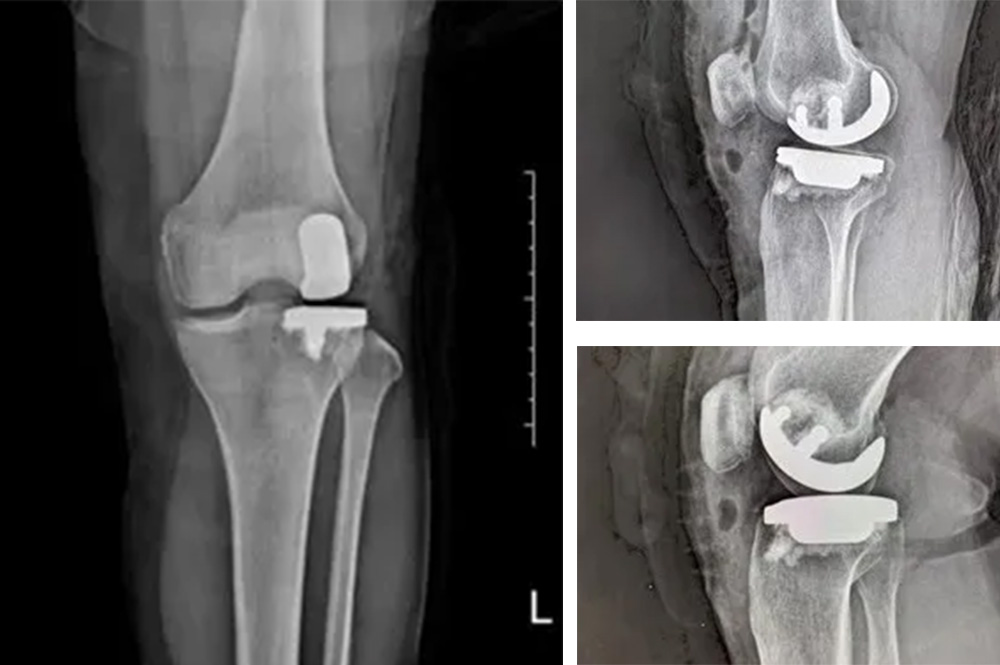

我院骨科主任羅醫(yī)生介紹,膝關(guān)節(jié)分為內(nèi)側(cè)、外側(cè)和髕股三個(gè)間室。鮑奶奶的問題主要集中在膝關(guān)節(jié)外側(cè)間室,而內(nèi)側(cè)和髕股關(guān)節(jié)相對(duì)完好。

“傳統(tǒng)全膝關(guān)節(jié)置換會(huì)切除所有關(guān)節(jié)面,而單髁置換只替換病變的部分,保留了健康的韌帶和軟骨,更符合‘精準(zhǔn)醫(yī)療’理念。”羅醫(yī)生說。

經(jīng)過詳細(xì)的體格檢查、影像學(xué)評(píng)估和三維重建,醫(yī)療團(tuán)隊(duì)確認(rèn)鮑奶奶的情況非常適合進(jìn)行膝外側(cè)單髁置換術(shù)。這種微創(chuàng)手術(shù)創(chuàng)傷小、恢復(fù)快,能夠最大程度保留膝關(guān)節(jié)的自然結(jié)構(gòu)和功能。

手術(shù)當(dāng)天,骨科團(tuán)隊(duì)采用微創(chuàng)切口,僅約8厘米,遠(yuǎn)小于傳統(tǒng)全膝關(guān)節(jié)置換手術(shù)切口。術(shù)中精準(zhǔn)定位,僅置換病變的膝關(guān)節(jié)外側(cè)間室。

手術(shù)使用了最新的單髁假體系統(tǒng),這種假體設(shè)計(jì)更符合人體工程學(xué),能夠更好地恢復(fù)膝關(guān)節(jié)的自然運(yùn)動(dòng)軌跡。